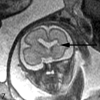

Fetal MR imaging is an increasingly available technique used to evaluate the fetal brain and spine. This is made possible by recent advances in technology, such as rapid pulse sequences, parallel imaging and advances in coil design. This provides a unique opportunity to evaluate processes that cannot be approached by any other current imaging technique and affords a unique opportunity for studying in vivo brain development and early diagnosis of congenital abnormalities inadequately visualized or undetectable by prenatal sonography. This 2-part review summarizes some of the latest developments in MR imaging of the fetal brain and spine and its application to prenatal diagnosis. This first part discusses the utility, safety, and technical aspects of fetal MR imaging, the appearance of normal fetal brain development, and the role of fetal MR imaging in the evaluation of fetal ventriculomegaly. The second part focuses on additional clinical applications of fetal MR imaging, including suspected abnormalities of the corpus callosum, malformations of cortical development, and spine abnormalities.